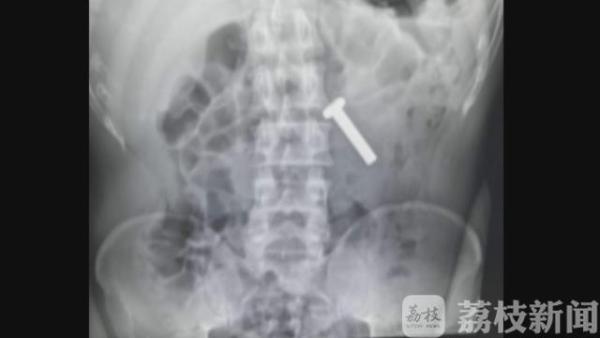

办案民警随赶紧将赵某带到医院做胃镜,发现他竟然生吞了一枚铁质螺丝钉,长约两厘米。原来,赵某曾经因为盗窃、吸毒等违法犯罪行为,被多次打击处理,深知警方办案流程。

据赵某交代,他了解到警方在关押犯人时,如果嫌疑人体内有异物,看守所是拒收的,这样他就能顺利变更强制措施为取保候审。事后,医生顺利的从赵某胃中,取出了这枚螺丝钉,赵某的计划落了空。